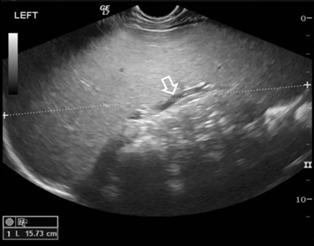

Figure 1: Abdominal

Ultrasound scan. Longitudinal image through the left hypochondrium shows

excessive splenomegaly. The spleen measures 15.7 cm (between cursors) with no

focal lesions and normal diameter of splenic vein (arrow)

fever subsided but anemia and excessive splenomegaly persisted (Figure 1). Mantoux, viral markers, blood and urine cultures were negative.